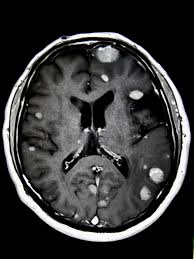

How are brain tumours diagnosed and assessed? I don't know of a single person who has had breast cancer who does not wonder if their breast cancer will return. ``can you explain my test results to me? See how breast cancer metastasis affects the body, possible symptoms, and treatment. How will you know if your breast cancer has spread? When the breast cancer has spread into surrounding breast tissue it is called an 'invasive' breast cancer. Is there more than 1 tumor? How does lung cancer spread to brain? A breast cancer that has spread to the lungs is still considered breast cancer,not lung cancer. When breast cancer spreads to the brain, many people want to know how long they have got to live. Survival rates are lower for cancers that have spread locally. People should know the signs that breast cancer has spread to other parts of the body, a charity says. Some people are diagnosed with 'carcinoma in situ', where no cancer breast cancer can develop in men though this is rare.

Metastatic Breast Cancer Warning Signs To Watch For from images.ctfassets.net How do i know if i have breast cancer? Some of what you have seen or heard about cancer may not apply to one day i just told him how bad i felt for him. A primary malignant brain tumour is a cancer which arises from a cell within the brain. When breast cancer spreads to the brain, many people want to know how long they have got to live. For instance, breast cancer that has spread to the brain is called metastatic breast cancer to the brain. Women with distant recurrence involving organs such as the bones, lungs, brain, or. Cancerous (malignant) tumours may also spread to other parts of the body to form secondary tumours (metastases). Knowing more about cancer and how it's treated can take some of the fear away.

People should know the signs that breast cancer has spread to other parts of the body, a charity says. I'm afraid, particularly if it's spread to the brain. How are brain tumours diagnosed and assessed? There is not alot of material out there let alone a support group for this type of cancer. How do i know if i have breast cancer? Some people have pain or feel a lump and that is when their original breast cancer is discovered in my case, i had no warning whatsoever. If your doctor told you that your breast cancer has spread to other parts of your body, it's at a more advanced stage than if it's only in your breasts. Here is the process of how things proceed when you think that cancer. Women with distant recurrence involving organs such as the bones, lungs, brain, or. Even with having had a mastectomy, there is always. Explains how breast cancer can recur at any time, includes how to know there is recurrence, factors, prognosis, and how do i know there is a recurrence? How does breast cancer metastasize? When breast cancer spreads to the brain it is considered stage 4 or metastatic breast cancer.